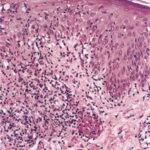

HISTOPATHOLOGY As with the morphology of the clinical lesions, pityriasis lichenoides can exhibit a range of histopathologic features encompassing acute, chronic, and intermediate lesional variants . All cases of pityriasis lichenoides contain an interface dermatitis that is denser and more wedge shaped in the acute lesions. The infiltrate is composed mainly of lymphocytes with a variable admixture of neutrophils and histiocytes. There is exocytosis, parakeratosis, and extravasation of erythrocytes. Epidermal damage ranges from intercellular and extracellular edema in less severe cases to extensive keratinocyte necrosis, vesicles, pustules, and ulcers. The acute variants can exhibit lymphocytic vasculitis with fibrinoid degeneration of blood vessel walls. Occasional CD30+ lymphoid cells and occasional atypical lymphoid cells may be seen as a non-specific finding in many cutaneous lymphoid infiltrates. The presence of an appreciable numbers of these cells is not consistent with classic pityriasis lichenoides of any type and should raise concern for the lymphomatoid papulosis-CD30+ anaplastic large cell lymphoma disease spectrum.74 Other immunohistologic features and the clonality of pityriasis lichenoides are discussed in Etiology and Pathogenesis. Differential Diagnosis The differential diagnosis of pityriasis lichenoides includes many papular eruptions . Those that develop crusts, vesicles, pustules, or ulcers are grouped with PLEVA, whereas those that form predominantly scaly papules are grouped with PLC. Most of them can be excluded based on history and typical clinicopathologic features. A few, such as secondary syphilis and viral-associated lesions, also can be excluded based on serologic tests. Among the most challenging diseases to distinguish from pityriasis lichenoides are lymphomatoid papulosis and macular or papular variants of MF. As detailed earlier, the presence of large atypical lymphoid cells (often CD30+) differentiates lymphomatoid papulosis from pityriasis lichenoides.Macular or papular variants of MF are rare. They exhibit classic features of MF, including small atypical epidermotropic lymphoid cells with convoluted nuclei and a band-like superficial dermal lymphoid infiltrate. Complications Secondary infection is the most common complication of pityriasis lichenoides. PLEVA may be associated with low-grade fever, malaise, headache, and arthralgia. Patients with PLUH can develop high fever, malaise, myalgia, arthralgia, and gastrointestinal and central nervous system symptoms. Occasionally, debilitated patients may die. PLC has been associated uncommonly with LPP in children. Despite